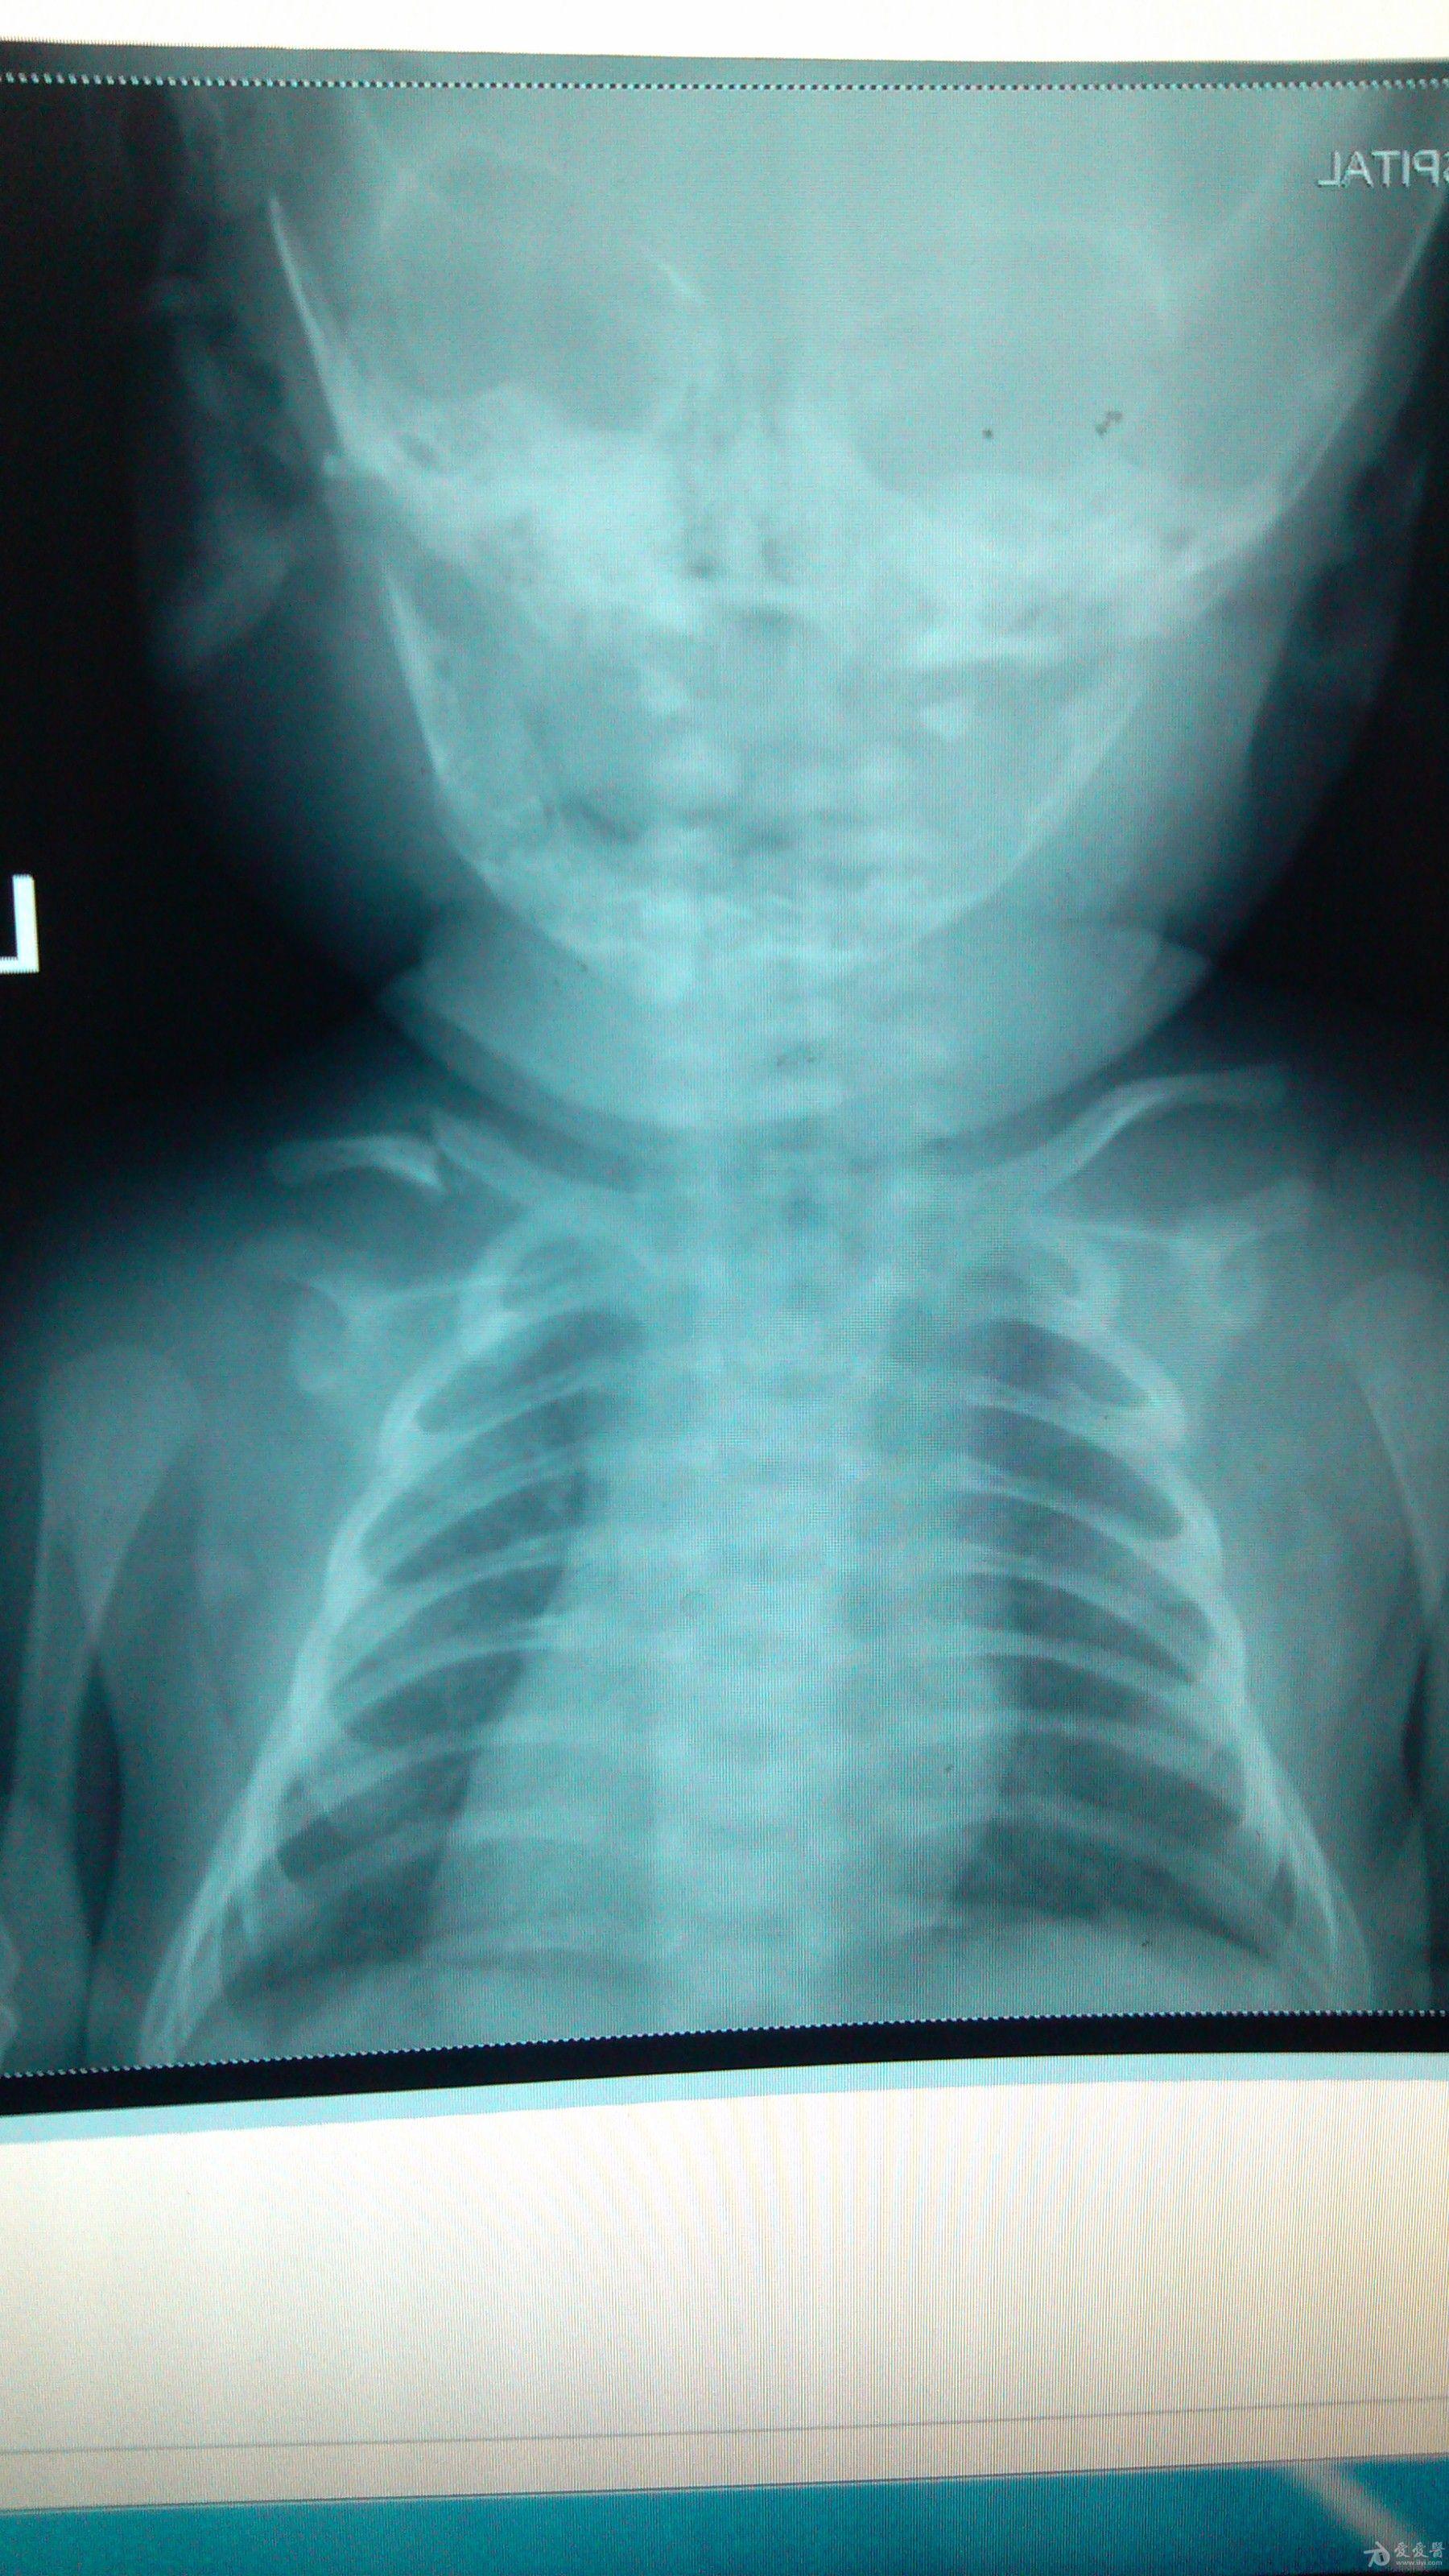

小儿锁骨骨折鼓包

小儿锁骨骨折鼓包,

新生儿锁骨骨折